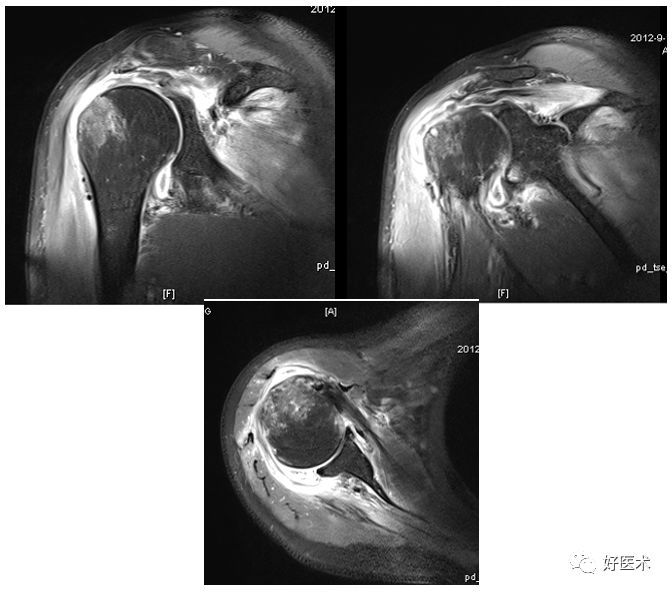

骨性Bankart病变

-

MR间接关节造影1.5T轴位T1W脂肪抑制(TR=460s,TE=90s)

SLAP、Bankart合并Hill-Sach损伤